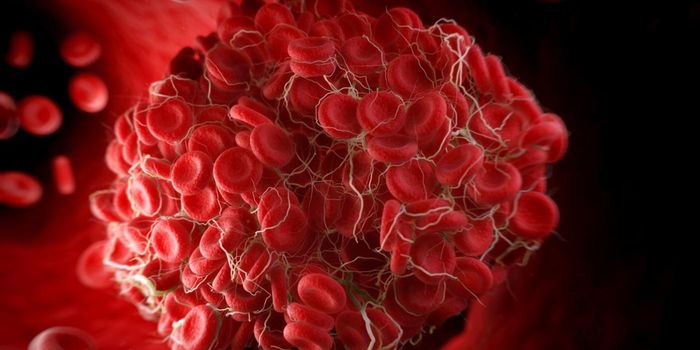

DEC 12, 2013MicrobiologyThe phrase "blood clot" rarely has a positive spin-most people associate blood clots with traumatic and potentially fata ...

NOV 09, 2017CardiologyBlood clots are normally seen as something to be avoided, something with dangerous consequences such as heart attack, st ...

SEP 17, 2020Clinical & Molecular DXBlood clotting, also known as coagulation, is a critical biological mechanism to prevent excessive blood loss in the eve ...

MAY 25, 2017CardiologyThe development of a blood clot could be very beneficial or very dangerous, depending on the situation. On one ha ...